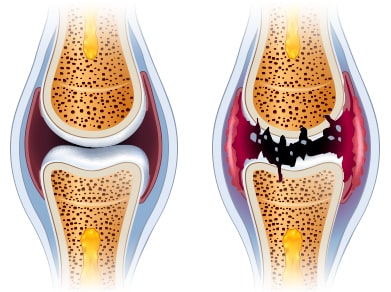

근육의 위축과 관절의 구축은 관절의 기형을 유발하게 되며, 관절의 연골이 닳아서 관절에 소리가 날 수 있습니다. 또한 관절의 열이 나거나 발적이 나타날 수 있고 관절이 변형되어 굽은 다리로 진행될 수 있습니다.

관절은 초기에 빨리 발견하기가 어렵다고 하는데 그 이유는 연골은 신경세포가 없기 때문에 손상을 입어도 자각하기가 쉽지 않기 때문입니다.